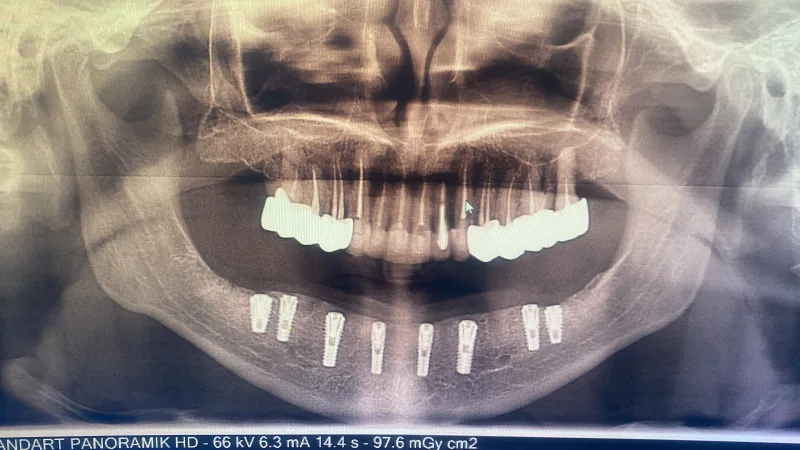

✅ 치아 보철 및 임플란트